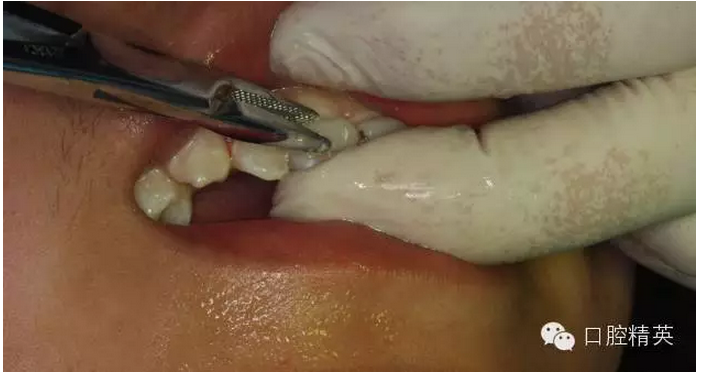

圖13.清理21牙槽窩

圖14.再植21離體牙